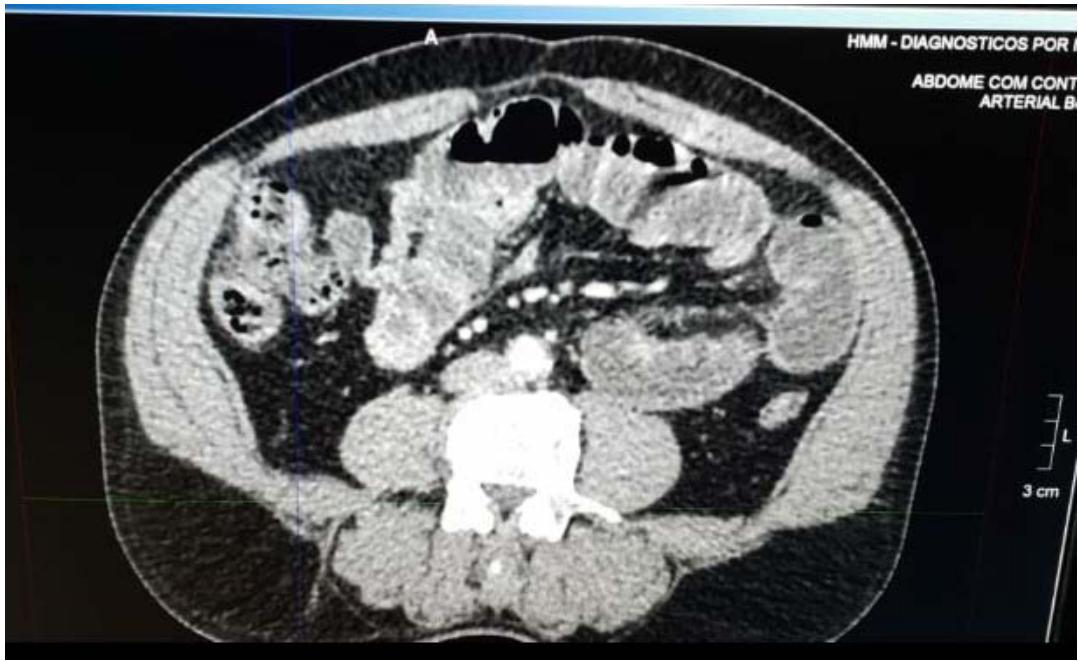

Apresentou: Hb 16,3 g/dl; VG de $49.3\%$; 12.650 leucocitos/mm3; 4% de bastões e 256.000 plaquetas e Proteina C reativa (PCR) de 19,8 mg/l (Referência: até 5mg/l). Tomografia Computadorizada (TC): "Discrete aumento do conteudo liquido/gasoso no intestino delgado com algunos níveis hidroáreos;PEGua quantidade de liquido livre na cavidade pelvica; diverticulos no sigmoide sem processo inflamatório". Paciente foi submetido à laparotomia exploradora por abdome agudo obstruito. No intra-operatório, identificado poucoera quantidade de liquido livre, grande distensão de todo o delgado, a partir do ângulo de Treitz até seu terço médio, com punto abrupto de aconteamento no qual a palpação identificou-se nódulo endurecido e aderida à luz intestinal, causando a obstruição. Realizada enterectomía segmentar com enteroenteroanastomose mecânia. Paciente iniciou dieta no segundo pos-operatório e receivebu alta no quinto pos-operatório, sem intercorréncias. No anató-mo-patológico da peça: "Neoplasia neuroendocrina bem diferenciada, grau 1 histológico (G1), medindo 0,5 cm no maior eixo, localizo em intestino delgado. A profundidade da invasão foi até a subserosa, com indices mitólico de 1 mitose/10 CGA e estadiamento patológico (TNM, 8a ed, 2017) pT3 pN0. Não foram detectados invasão angiolinfática, necrose tumoral, infiltração perineural, depositos tumorais em mesentério. A margem cirúrgica proximal e distal estavam livres e a margem cirúrgica radial está vivre e distando 1,5 cm da lesão. O tecido adiposo mesentérico está vivre de neoplasia".

a) Elementos De Apoio Para Analise Dos Resultados E Discussao i. Tabelas, quadros, figuras e quadros: Imagem 1: Tomografia Computadorizada (TC) do caso relatado tomografia computadorizada (TC), ultrasonografia endoscópica e endorretal (USER), ressonência nuclear magnética (RNM) e videocápsula endoscópica pode ser úteis para diagnóstico, localização e estadiamento da doença.[24]